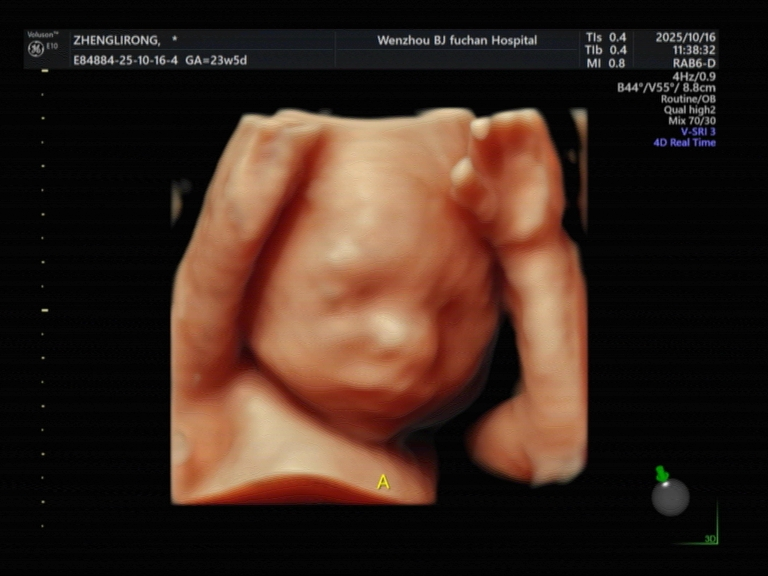

做四维彩超双胞胎为什么产检费用很贵?

简单来说,做一例双胞胎四维彩超,其工作量、技术难度、时间消耗和医生所承担的压力,都远非单胎检查的简单“翻倍”。